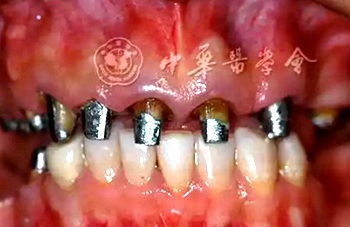

口腔衛(wèi)生狀況一般,菌斑指數(shù)0~2,鄰面少量軟垢;牙齦齦緣鮮紅、水腫、質(zhì)軟,出血指數(shù)2~3,余牙牙齦輕度水腫,出血指數(shù)0~2;全口探診深度2~3 mm,個別位點探診深度達(dá)4~5 mm,鄰面可探及附著喪失;未查及牙齒松動及根分叉病變;烤瓷固定橋修復(fù),冠邊緣密合度欠佳,位于齦下1~2 mm;、唇側(cè)崩瓷,邊緣暴露;上前牙牙齦線不協(xié)調(diào);缺失,右下后牙可摘局部義齒修復(fù),固定橋修復(fù);近中面銀汞充填,近中懸突及繼發(fā)齲;上前牙覆蓋下前牙牙冠的1/2~2/3(圖1)。

圖1 患者初診時臨床照片 A:正面微笑像;B:正面口內(nèi)像

(1)唇齒齦關(guān)系:患者微笑時顯露全部齦乳頭及部分齦緣外形,為中位微笑[5]。牙列中線相對面中線稍偏左側(cè)。

(2)白色美學(xué)問題:上中切牙寬長比及上前牙寬度比雖均在正常范圍內(nèi),但外觀不理想;原有修復(fù)體崩瓷,左右兩側(cè)同名牙修復(fù)體外形及大小不對稱;上前牙接觸區(qū)過長,牙體長軸過于偏向遠(yuǎn)中。

(3)粉色美學(xué)缺陷:上頜前牙區(qū)左右兩側(cè)牙齦腫脹且形態(tài)不對稱、牙齦線不協(xié)調(diào),牙齦乳頭水腫、圓鈍;雙側(cè)牙齦頂點位置不對稱,牙齦頂點高于。